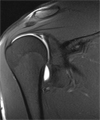

Die Magnetresonanztomographie (MRT) als wichtigste Modalität der Gelenkuntersuchung besitzt einen sehr hohen Weichteilkontrast. Hierdurch gelingt eine exzellente Beurteilung von Gelenkstrukturen wie Knorpel, Menisci und der Bänder. Weiterhin kommen Veränderungen an Muskeln und Sehnen, aber auch peripherer Nerven sehr sensitiv zur Darstellung.

Weiterhin ist es für Spezialuntersuchngen wie die MR-Arthrographie nötig.

Hierbei wird Kontrastmittel direkt in das Gelenk injiziert um schwer erkennbare Verletzungen der Binnenstrukturen sichtbar zu machen.